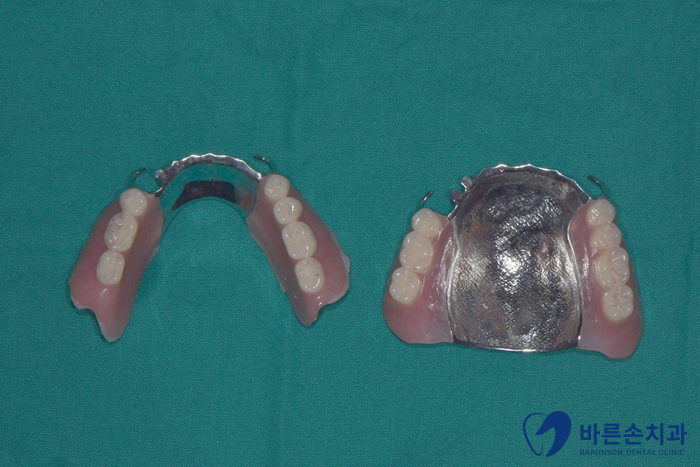

이제 이 상태에서 본을 떠서 부분틀니를 제작합니.

임플란트 치아에 부분틀니까지 완성된 구내 사진입니다.

무너졌던 교합고경도 높여드려 안모도 개선되고 더 젊어보이게 바뀌셨습니다.^^